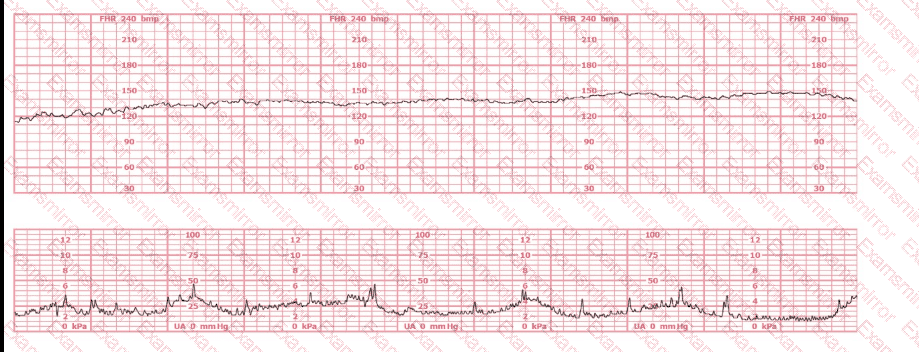

A woman (G1, P0) at 41-weeks gestation presents to OB triage to rule out labor. Her cervical exam is 1 cm/50%/-2. Membranes are intact. She would like to go home if not in labor. Based on this tracing, which represents the last two hours, the best approach is: